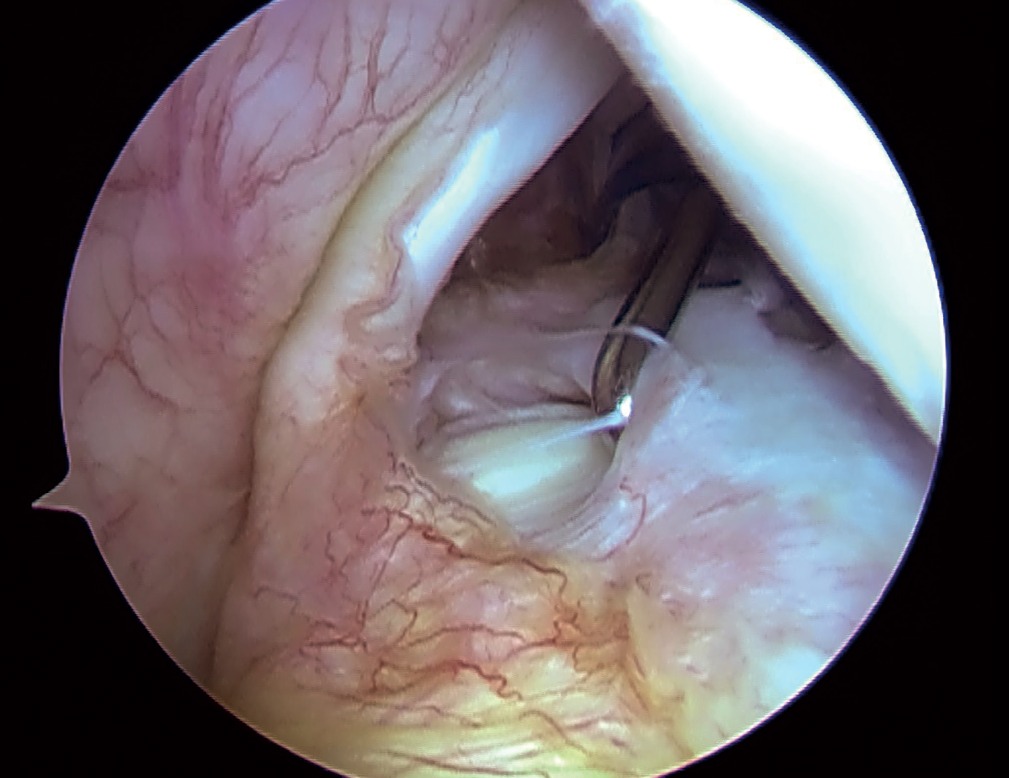

Arthroscopic view of the glenohumeral cavity of a right shoulder from the posterior portal, in a female patient operated upon due to relapsing shoulder dislocation. The photo shows a type 3 SLAP lesion of the bicipitolabral complex according to the classification of Snyder. This type of lesion is characterised by a bucket handle tear of the upper labrum, keeping the tendon of the long portion of the biceps intact.